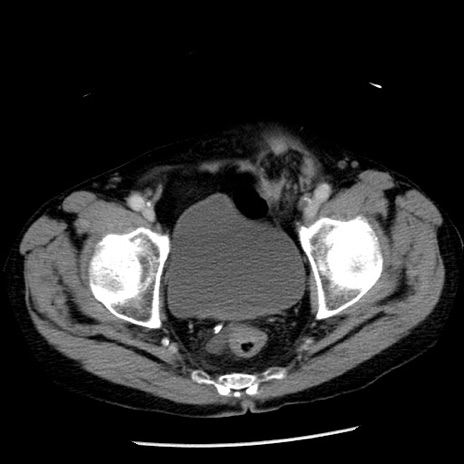

症例26(横断像)

【症例】80歳代男性

【主訴】嘔吐

【現病歴】昨晩2回嘔吐あり、今朝になっても嘔吐あり。来院。

【既往歴】胃潰瘍

【身体所見】意識清明、BT 37.6℃、BP 166/95mmHg、HR 100bpm、SpO2 97%、腹部:平坦・軟、腸蠕動音聴取良好、圧痛なし。

【データ】WBC 21900、CRP 1.46